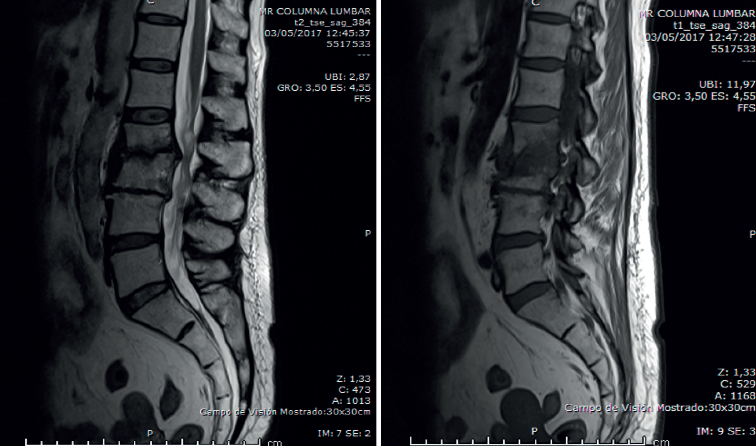

• Resonancia magnética (RM) lumbar (Figura 2): sagitales con secuencias T2 y STIR. Espondilodiscitis aguda con absceso en canal raquídeo y prevertebral.

Figura 2. Resonancia magnética sagital T2 y STIR.